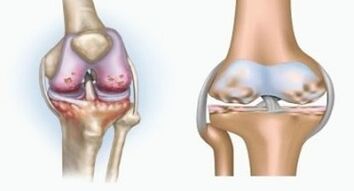

Bi patologiek artikulazioetan eragina dute, baina aldaketen izaerarekin desberdinak dira.

Artritisa ehun konektiboaren hantura da - ontzi asko dituen mintza sinovial bat eta linfo fluxua eskaintzen du. Hanturazko prozesuak ehun artikuluen elikadura urratzea dakar, eta ondorioz, lubrifikazio artikulatuaren produkzioa da.

Arrosia

Artrosia, artikulazioaren kartilagoen ehunak suntsitzearekin lotutako prozesu degeneratiboa da. Kartilagoa pixkanaka suntsitzen da, lehorra, bateratuen hezurren arteko distantzia gutxitzen da, eta horrek mina kausa da. Forma larrietan suntsipenak hezurrak eragiten ditu. Porotsuagoak bihurtzen dira, dentsitatea galdu, hauskorra bihurtu.

Adibidez, zein da belauneko artikulazioaren artritisaren eta artrosiaren arteko aldea? Artritisarekin, ehun artikuluen maskor sinovial gertatzen da. Horrek tenperaturaren gehikuntza eragiten du artikulazioan.

Elkarguneak, mina sindrome iraunkorra garatzen da, mugimenduan zehar areagotuz. Artrosez, mina jarduera fisikoa egin ondoren gertatzen da, artikulazioan egindako krisi edo klik bat entzun ahal izango duzu, pixkanaka juntura deformatu eta mugikortasuna galtzen du.

Kartilagoaren eta hezur-ehunaren porrota ahaztutako egoeran dagoen etapetan gertatzen da. Artrosia, kartilagoaren ehuna lehenik eta behin, hezurrak, mintz sinovialaren hantura bigarren mailako jatorria da, hau da, haien aurrekariak garatzen ditu.